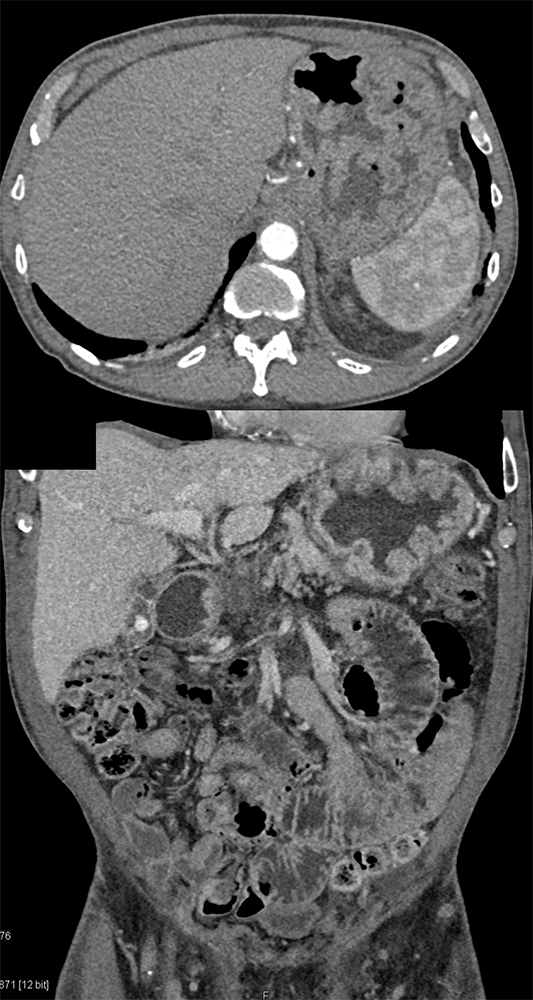

Perforated Benign Gastric Ulcer ![]() |